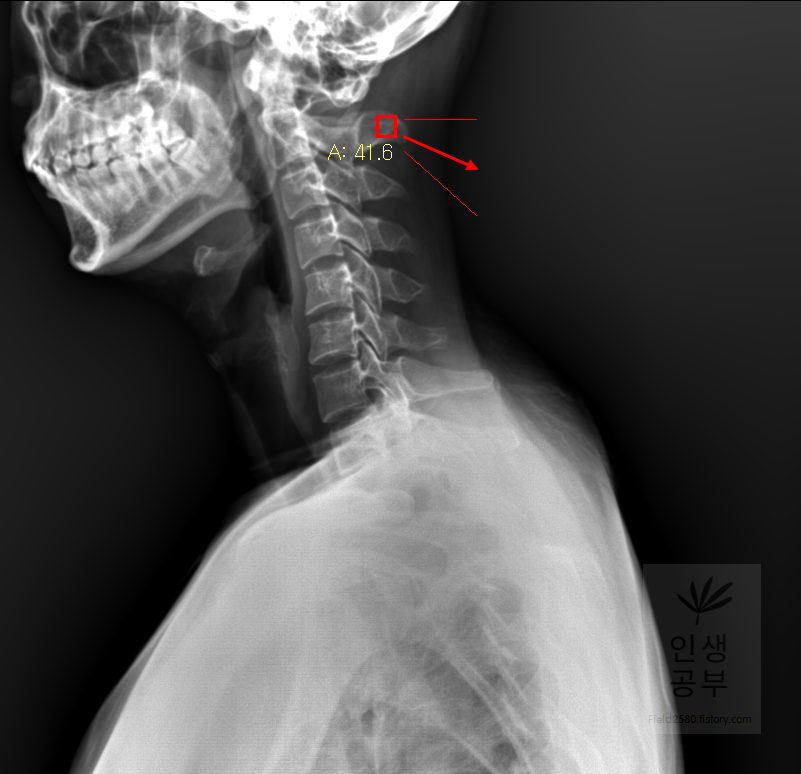

선 긋기를 이용해서 Cobb각을 그린다고 가정했을 때 측정하려고 하는 곳을 처음에 누르고 드래그로 쭉 끌어다주면 위와 같은 선이 생기고 선의 길이가 자동으로 측정됩니다. 첫 번째 목뼈(C1) 선을 그리기 위해 제일 튀어나온 앞쪽 부분 가운데 지점에(Center of Anterior arch) 점을 찍어줍니다. 후궁(Posterior arch) 제일 좁은 부위 가운데 지점에 점을 찍어줍니다. 두 점을 연결해주는 선을 그어줍니다. 이 선 이름을 고리 뼈 선(APL : Atlas Plane Line)이라고 합니다. 점은 조금 더 정확하기 위해서 하는 것이 찍어도 되고, 점을 찍지 않은 상태에서 선을 그으셔도 무방합니다.

일곱번째 목뼈 추체 밑면(Inferior endplate of C7)과 평행한 선을 그어줍니다.

두 선사이에 수직인 선을 그어야 하기 때문에 각도기 모양이 있는 버튼을 눌러줍니다.

위쪽 선을 따라서 선을 긋고 90도를 맞춰서 선을 그어줍니다. 동그라미 표시된 곳을 먼저 찍어주고, 화살표를 따라서 위쪽 선을 따라서 그려주고, 90도 방향에 맞춰서 아래로 그어줍니다. 노란색 글자와 숫자가 아래줄 맞춰 준 곳에 있는데 A는 Angle 각도이고 옆에 있는 숫자가 현재 긋고 있는 각도의 값입니다

아래 선을 따라서 선을 긋고 90도에 맞춰서 선을 그어줍니다. 동그라미 표시된 곳을 먼저 찍어주고, 화살표를 따라서 아래쪽 선을 따라서 그려주고 90도 방향에 맞춰서 위로 그어줍니다. 위쪽 선에서 그은 선과 교차되게 그어주시면 됩니다.

두 선이 교차된 곳에서 각도가 생기게 됩니다. 이 각도를 Cobb 각이라고 합니다. 위쪽에 각도를 재거나 아래쪽에 각도를 재어도 똑같으니 원하는 방향의 각도를 측정해 주시면 됩니다. 각도를 측정할 때에는 두선이 교차한 곳에 먼저 클릭해주고 위 화살표 방향대로 오른쪽 왼쪽의 교차한 선을 따라서 측정해 주시면 됩니다. 왼쪽선을 먼저 그어도 되고 오른쪽 선을 먼저 그어도 상관없습니다.

위쪽에 있는 선은 첫 번째 목뼈(C1) 선을 그리기 위해 제일 튀어나온 앞쪽 부분 가운데 지점에(Center of Anterior arch)에서 시작해서 후궁(Posterior arch) 제일 좁은 부위 가운데를 지나는 선이 되도록 이동해줍니다. 선 이름을 고리 뼈 선(APL : Atlas Plane Line)이라고 합니다. 점은 조금 더 정확하기 위해서 하는 것이 찍어도 되고, 점을 찍지 않은 상태에서 선을 그으셔도 무방합니다. 아래쪽에 있는 선은 일곱번째 목뼈 추체 밑면(Inferior endplate of C7)과 평행하게 선을 맞춰줍니다. 노란색 글자와 숫자가 아래줄 맞춰 준 곳에 있는데 A는 Angle 각도이고 옆에 있는 숫자가 Cobb 각입니다.